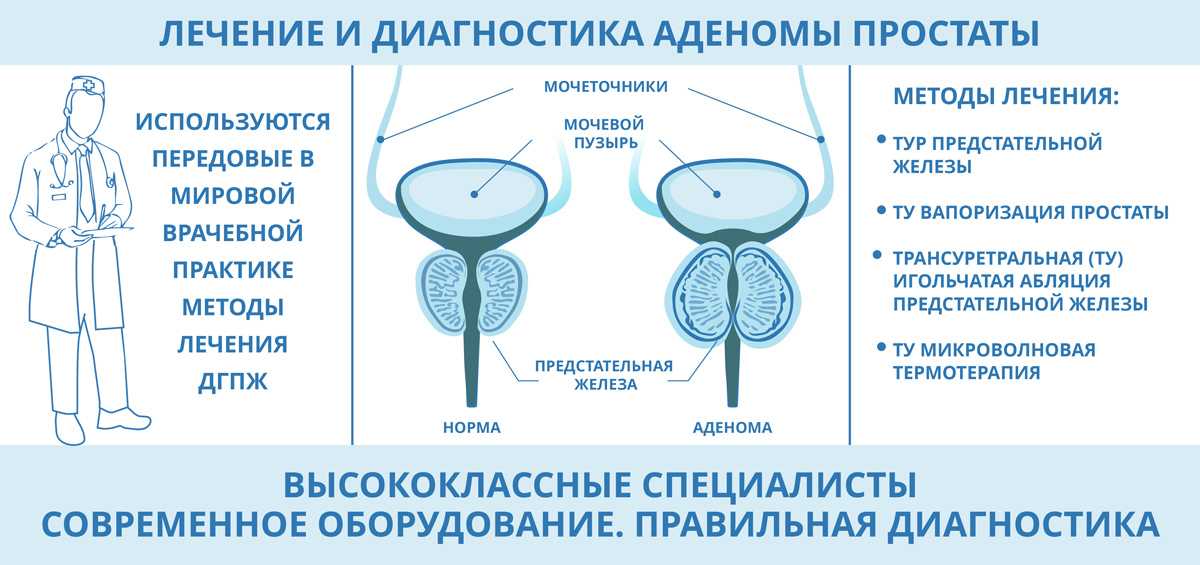

Простата, обычно ассоциируемая с мужским здоровьем после полового созревания, также присутствует у детей, хотя и в значительно меньших размерах. Этот орган, расположенный под мочевым пузырем и окружающий уретру, играет роль в выработке жидкости, которая составляет часть семенной жидкости. Несмотря на то, что проблемы с простатой у детей встречаются редко, понимание её развития и потенциальных патологий важно для ранней диагностики и лечения.